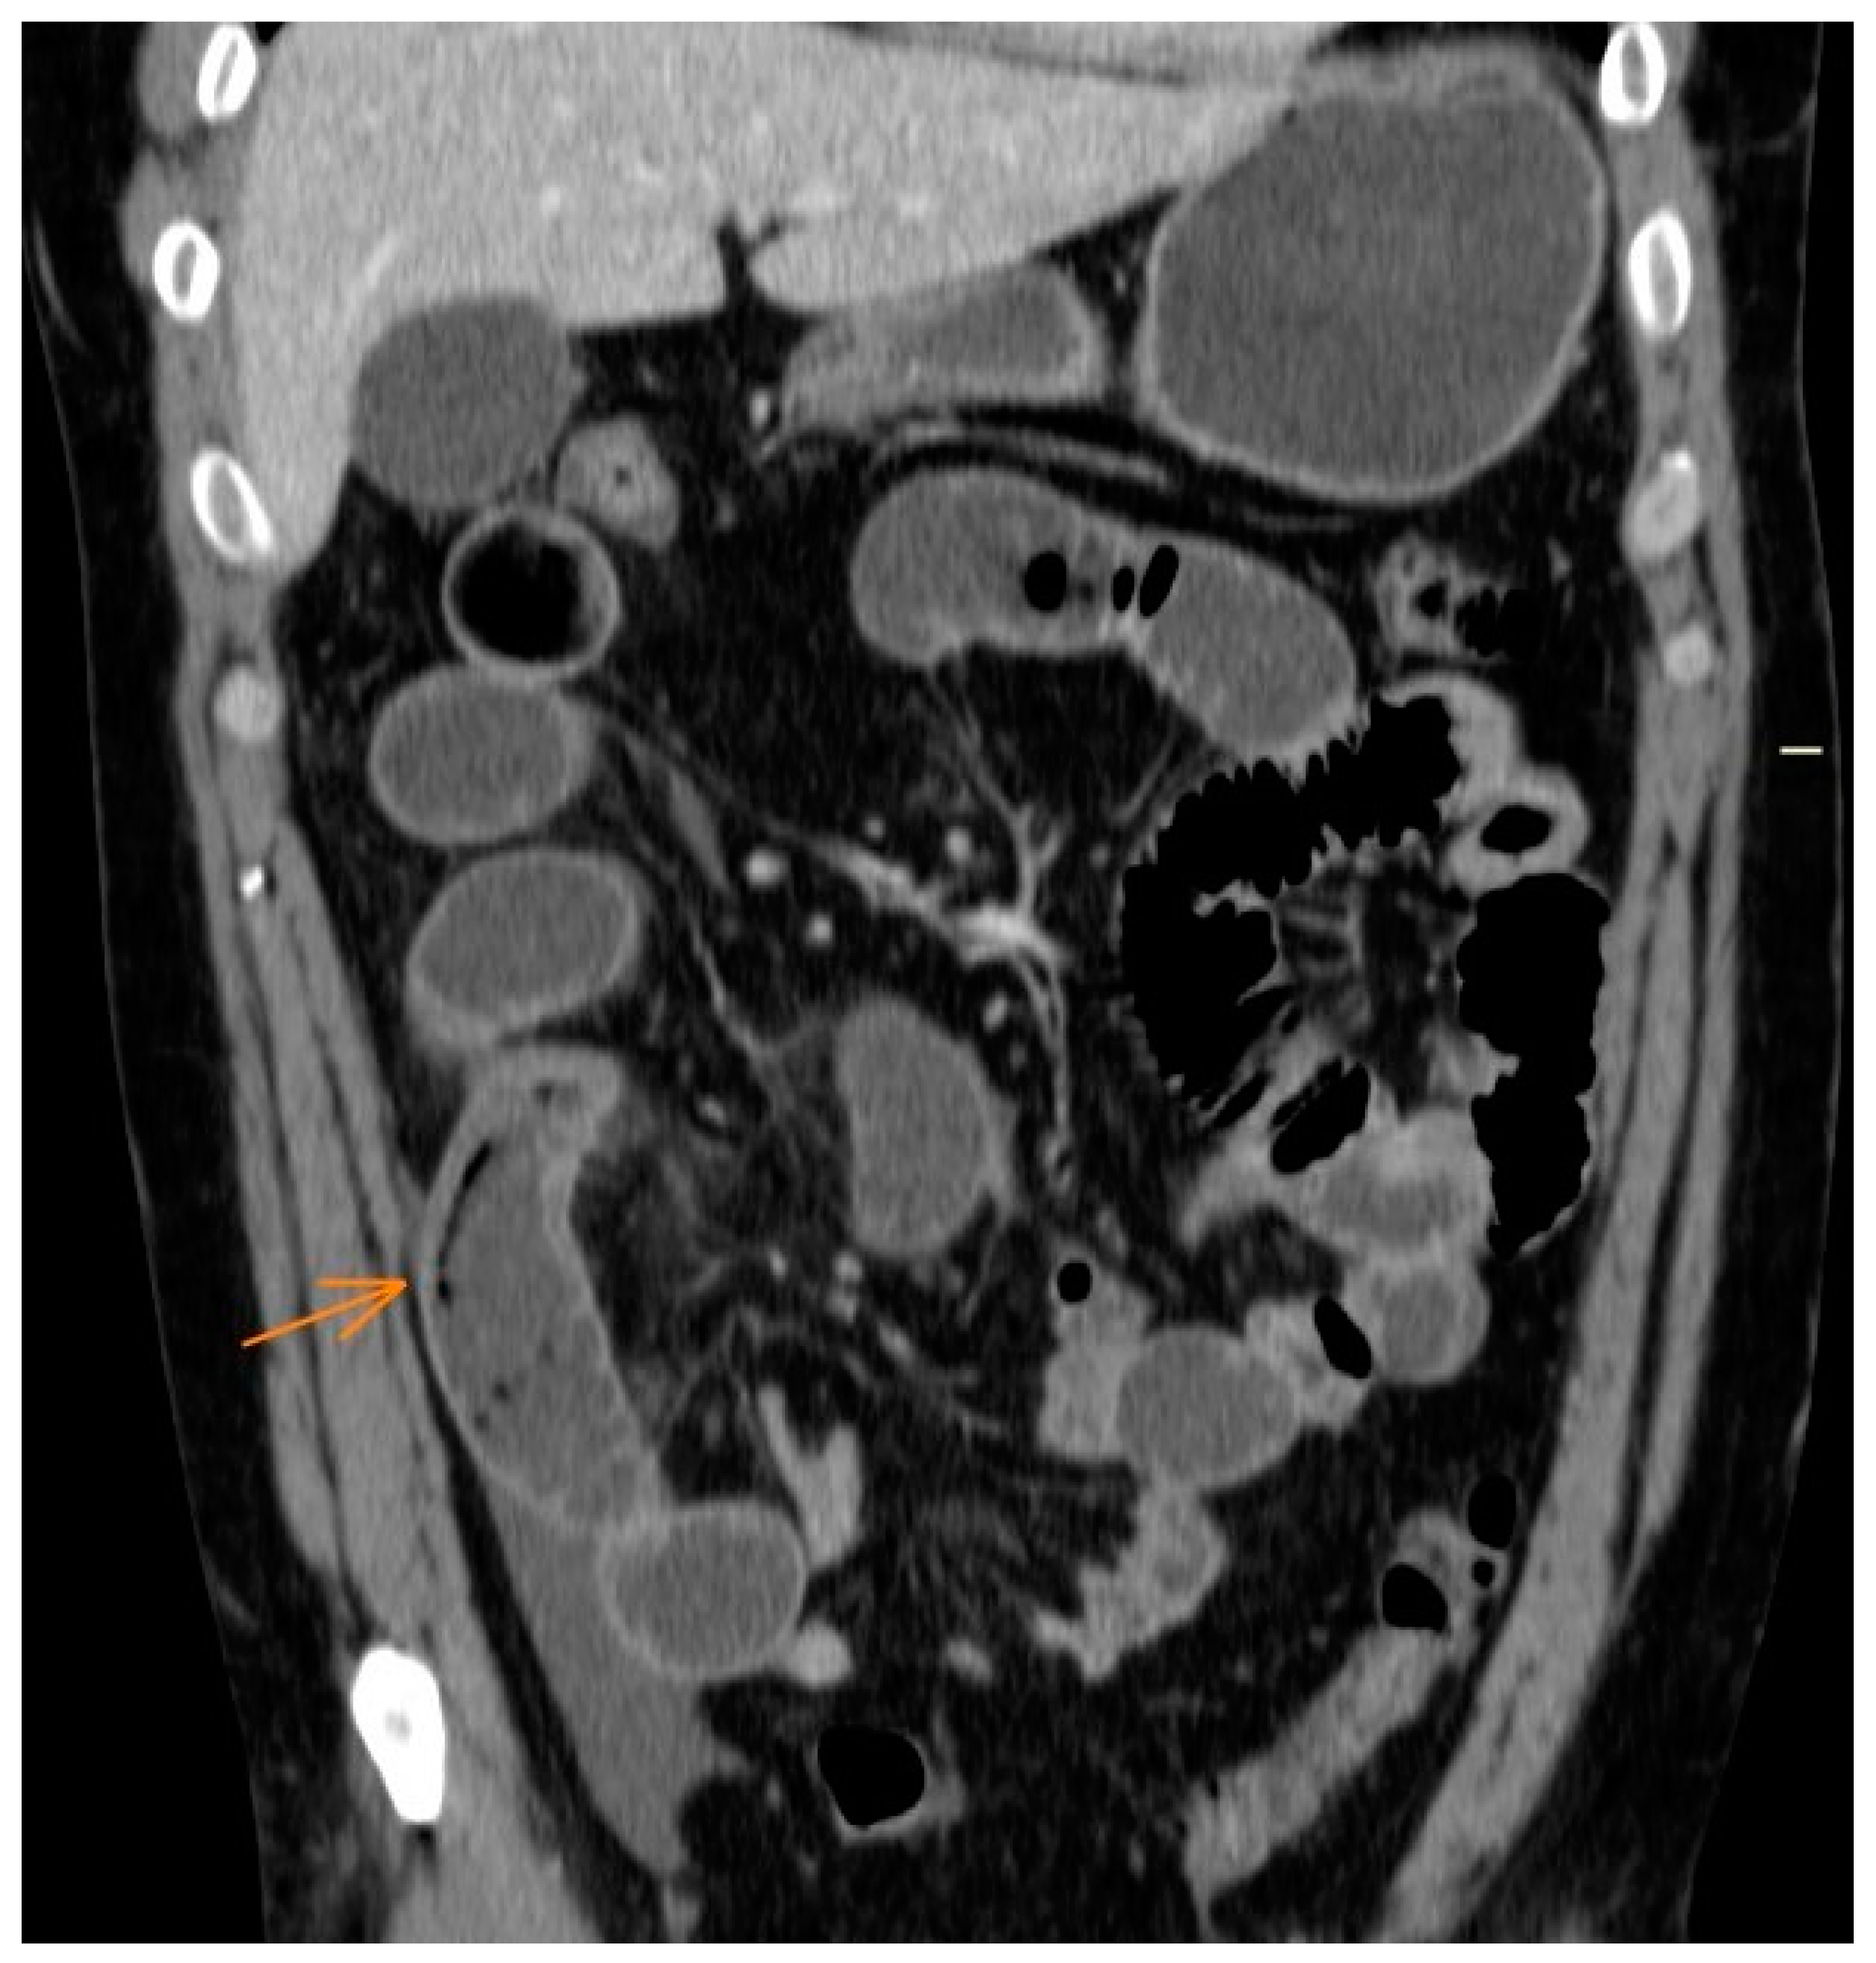

2. Case Description

- Shibata, E.; Ueda, T.; Akaike, G.; Saida, Y. CT Findings of Gastric and Intestinal Anisakiasis. Abdom. Imaging 2014, 39, 257–261. [Google Scholar] [CrossRef]

- Fornell Pérez, R.; Urizar Gorosarri, M.; Pérez Bea, M. Anisakiasis: Imaging findings. Radiologia 2022, 64, 245–255. [Google Scholar] [CrossRef] [PubMed]